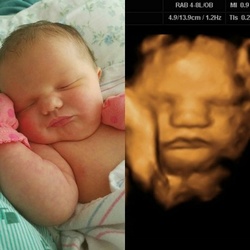

De multe ori, imaginile din timpul sarcinii corespund și cu realitatea de… după naștere. Astfel, cei de la BabyCenter au făcut o selecție specială a unor fotografii primite de la părinți: colaje cu imaginile din timpul ecografiilor și cele cu bebelușii la scurt timp după naștere. Sunt imagini spectaculoase care demonstrează cât de mult își păstrează prichindeii din limbajul trupului din timpul vieții intrauterine. În afară de trăsături și grimase...

Intră în galeria foto și vezi cele mai reușite colaje!